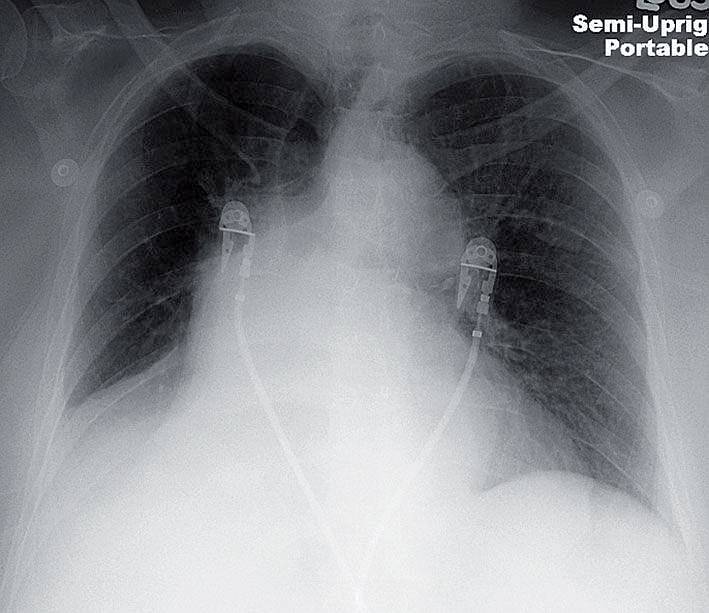

69-year-old woman with hemoptysis

69-year-old woman is admitted for hemoptysis.

What do you see on the chest x-ray ?